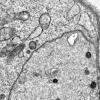

PERIPHERAL NEUROPATHY

7B CIDP (7)